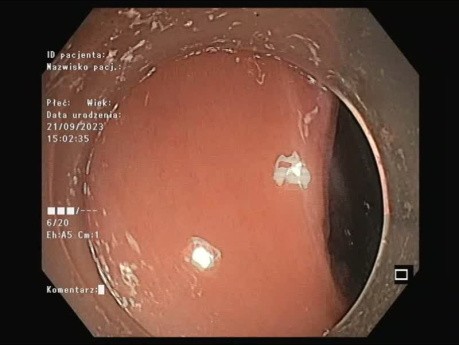

Duża zmiana o morfologii LST -G typu mieszanego...

Duża zmiana o morfologii LST-G typu mieszanego zlokalizowana 40 cm od odbytu na zagięciu z widoczną znaczną ruchomością oddechową. Zabieg rozpocęto od bocznego nacięcia. Następnie kontynuowano mukozektomię...